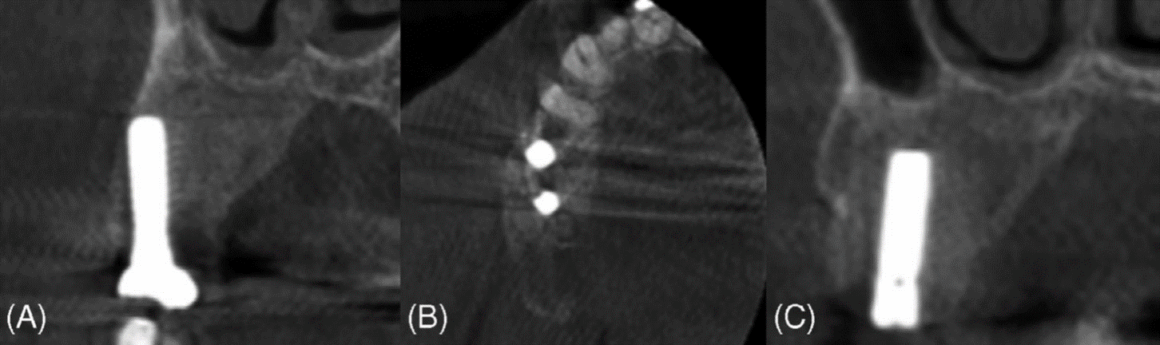

La alteración del contorno del hueso alveolar, la reabsorción o dislocación dental, las relaciones interarcadas anormales y la remodelación de la estructura ósea displásica con el tiempo plantean retos importantes para la rehabilitación oral. Las pruebas sugieren que los implantes dentales pueden tener una alta tasa de supervivencia en pacientes con DF. Una revisión sistemática realizada por Pérez et al. informó de una tasa de supervivencia del 100 % para 36 implantes durante un período de seguimiento medio de 51 meses (4,25 años). Además, un estudio de caso realizado por Monje et al. documentó el éxito de la colocación de un implante en el maxilar izquierdo de un paciente tras Tratamiento DF. Se extrajeron los premolares y el primer molar del paciente y, diez meses después de la extirpación de la lesión, se colocaron implantes. Un periodo de seguimiento de un año mostró una osteointegración satisfactoria, sin signos de inflamación, pérdida ósea ni movilidad. Además, un estudio de caso realizado por Monje et al. documentó el éxito de la colocación de implantes en el maxilar izquierdo de un paciente tras el tratamiento de la DF. Se extrajeron los premolares y el primer molar del paciente y, diez meses después de la extirpación de la lesión, se colocaron los implantes. Un periodo de seguimiento de un año mostró una osteointegración satisfactoria, sin signos de inflamación, pérdida ósea ni movilidad.

La DF representa un subconjunto de diversas displasias óseas que pueden afectar al hueso alveolar, lo que plantea retos únicos en la cirugía oral y maxilofacial. Esta afección altera el proceso normal de remodelación ósea, lo que provoca cambios significativos en la estructura y la estabilidad del hueso. Por consiguiente, es fundamental comprender cómo las displasias óseas como la DF afectan a la osteointegración y a la supervivencia a largo plazo de los implantes dentales. Evaluar los efectos de estas lesiones en el éxito de los implantes es clave para optimizar los resultados de los pacientes y desarrollar estrategias de tratamiento personalizadas. En este caso, un paciente con DF monoestótica en el lado derecho del maxilar superior fue tratado con éxito remodelando toda la lesión y conservando los implantes dentales. Los implantes no mostraron signos de movilidad clínica ni de recurrencia de la enfermedad.